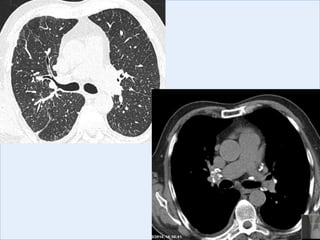

CXR

CT

Imaging: thickened interlobular septa, ground glass

infiltration, and honeycombing in a sub-pleural and

basal distribution

Investigations FEV1 2.25L (9%predicted) FVC 2.74L (65% predicted) ratio 0.82 Total lung volume 79% predicted, TLCO 48% predicted. CXR CT